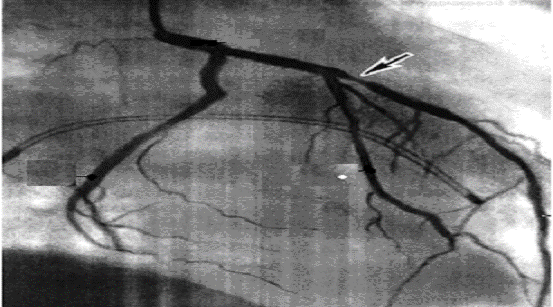

ÏÐÈËÎÆÅÍÈÅ 4

Ðèñ. 3. Àíãèîãðàôèÿ êîðîíàðíûõ ñîñóäîâ.